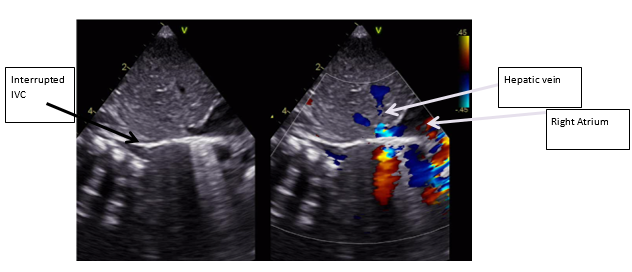

Postnatal ECHO revealed an Interrupted IVC (Figure 1) with venous return via the azygos vein (Figure 2 & Figure 3), draining into the superior vena cava (SVC), hepatic veins draining directly into the right atrium (RA), SVC draining into the RA and a small patent foramen ovale (PFO) with left-to-right shunting with normal cardiac anatomy with no abnormalities of the valves, aortic arch, outflow tracts, and no outflow tract obstruction.

Figure 1: Subcostal echocardiographic view demonstrating absence of Retrohepatic IVC (Interrupted IVC) with hepatic venous drainage directly into the right atrium.